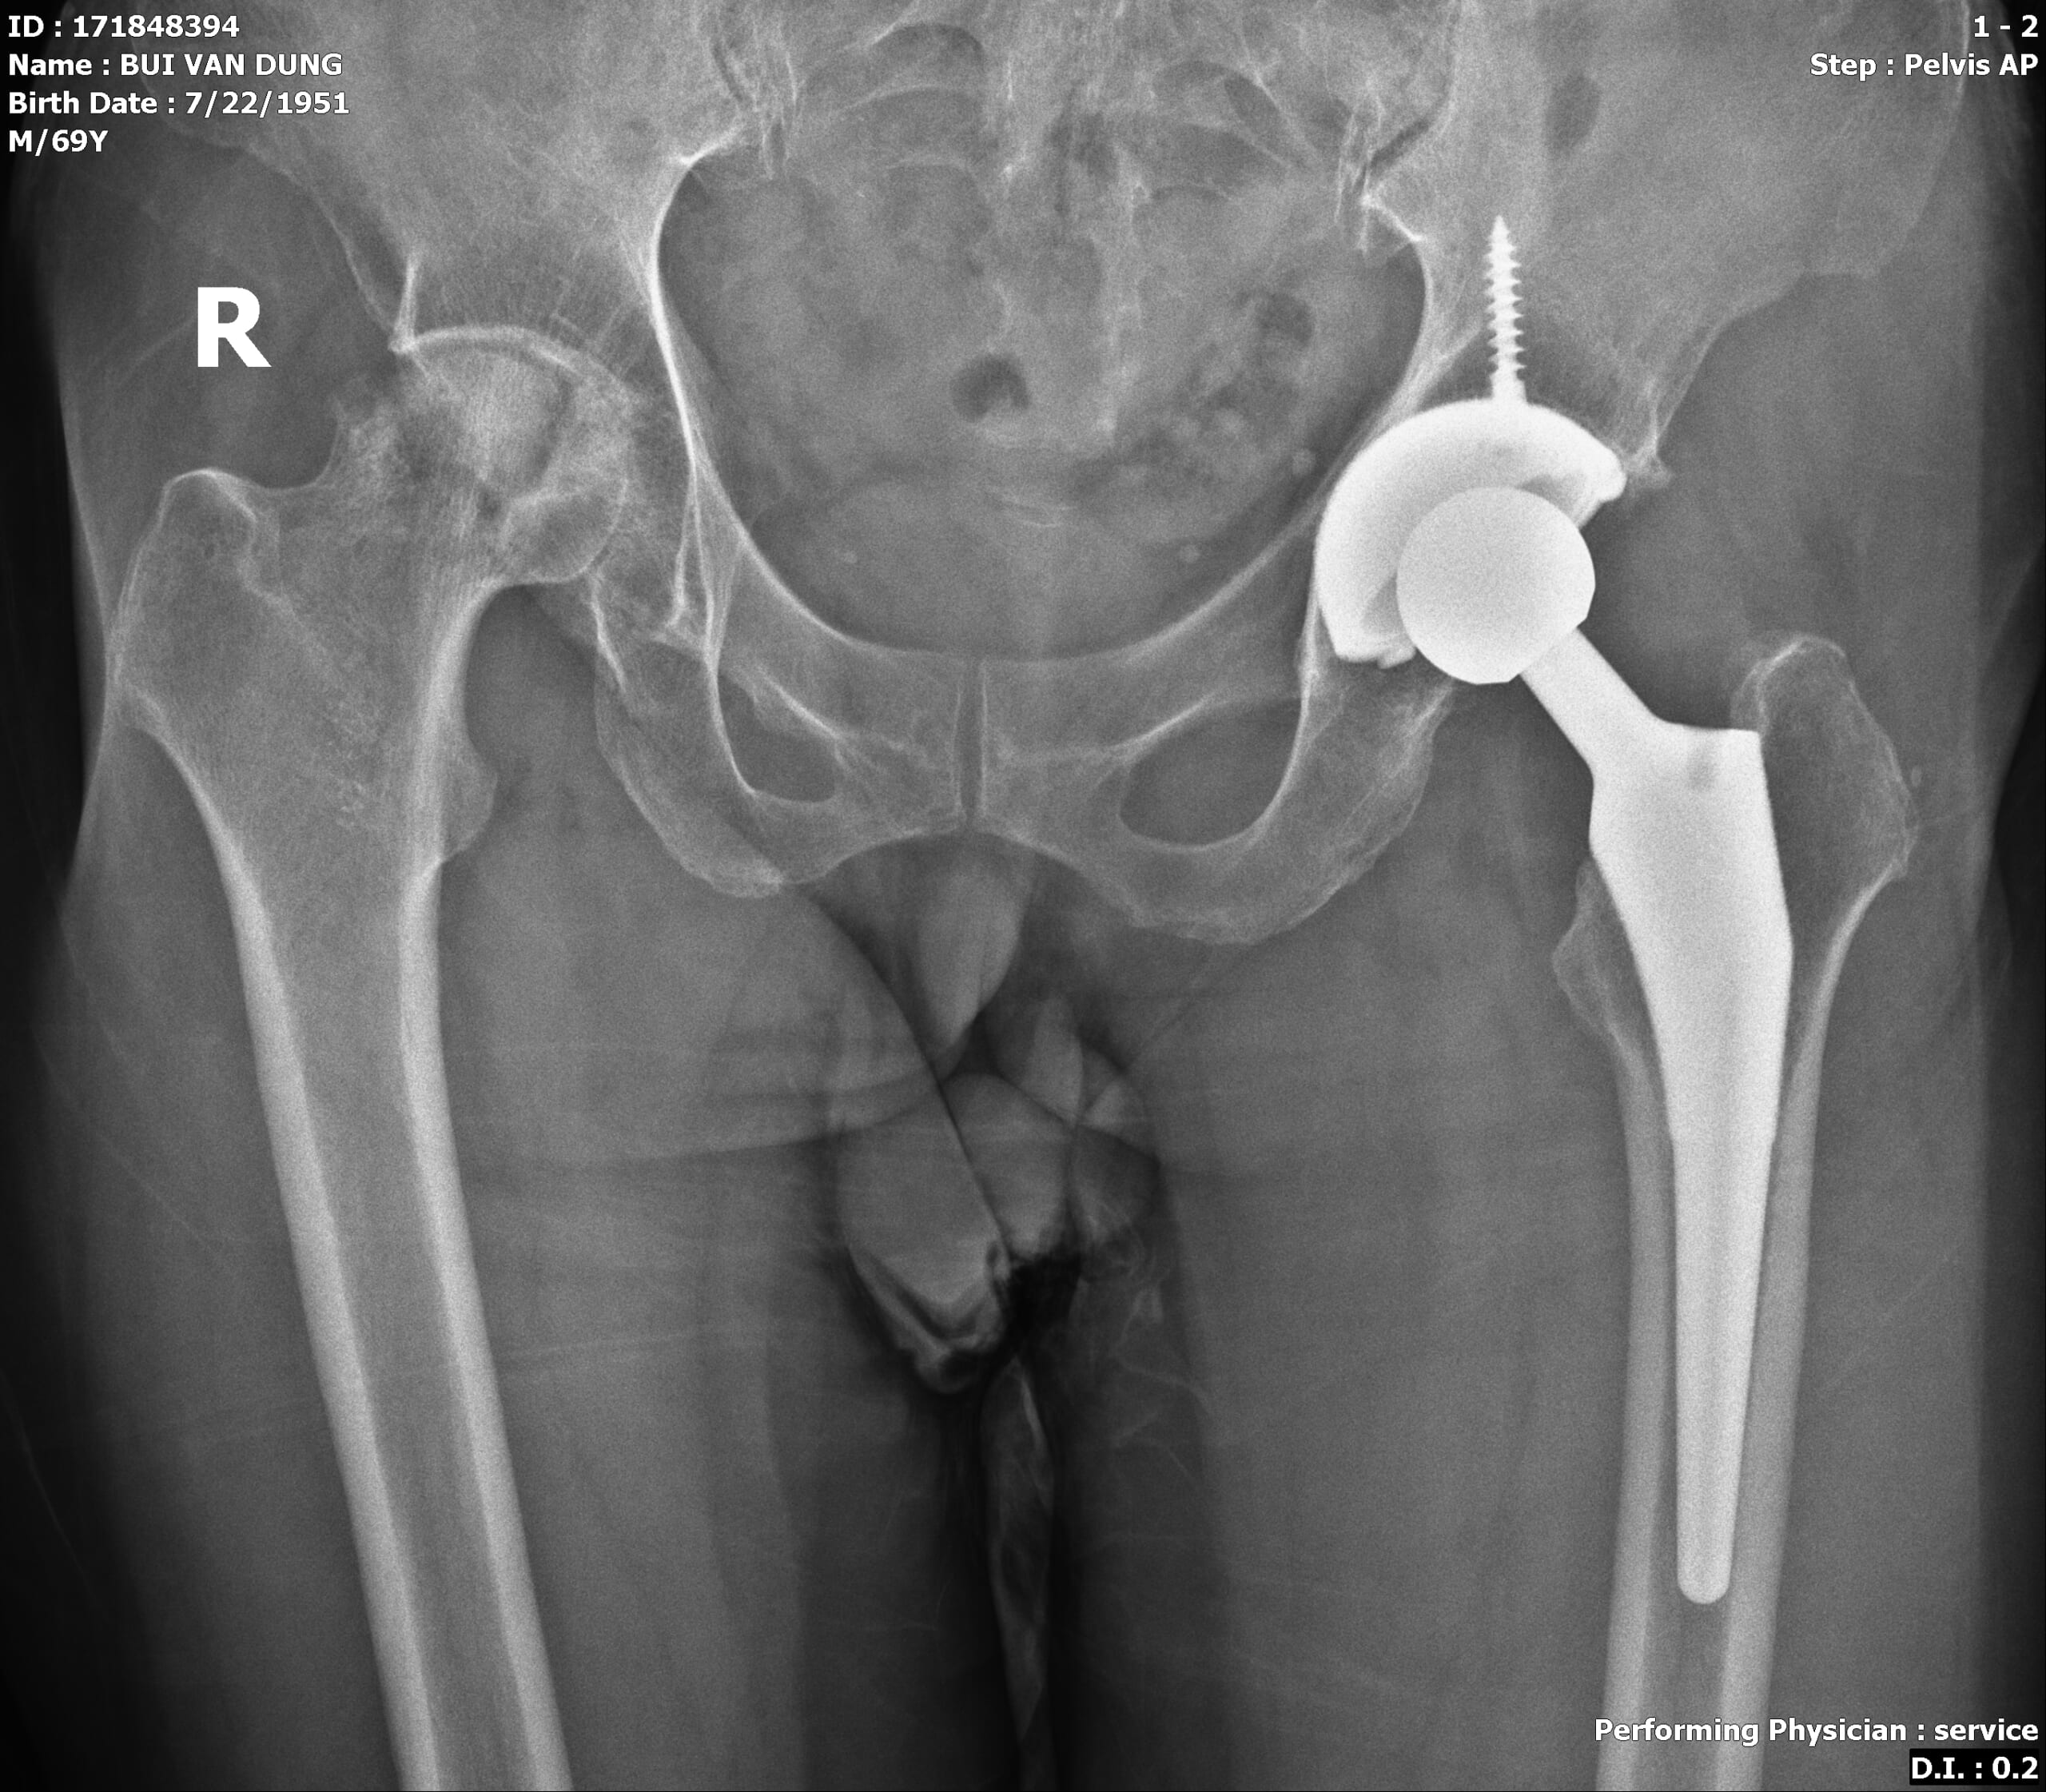

thoai hoa khop hang Ảnh: Hình ảnh phim X-quang khớp háng (phải) bị thoái hóa và khớp háng (trái) bị thoái hóa đã được thay khớp háng nhân tạo của bệnh nhân Bùi Văn Dũng (70 tuổi)

Phẫu thuật thay khớp háng trái thành công sau khoảng nửa năm, bệnh nhân tiếp tục được phẫu thuật thay khớp háng phải do có biểu hiện đau tăng lên và kết quả thăm khám cũng như chẩn đoán hình ảnh cho thấy tình trạng thoái hóa khớp háng phải đã tiến triển nặng.

Sau hai lần bệnh nhân được phẫu thuật thay khớp háng (trái và phải), hiện chân trái đã vận động bình thường, chân phải đang trong quá trình hồi phục. Bệnh nhân đã có thể đứng lên thực hiện các bài tập đi và vận động nhẹ nhàng.